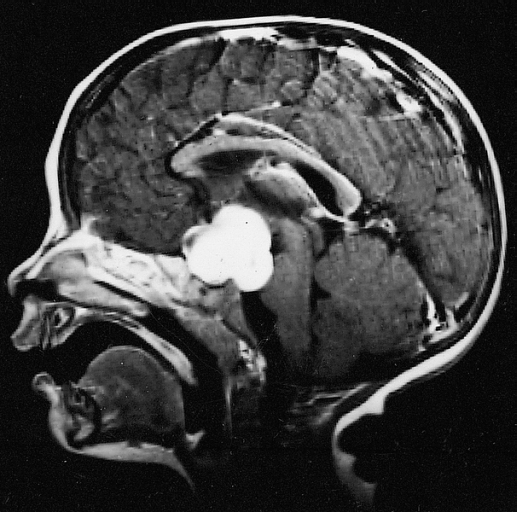

星形细胞瘤是始于星形脑细胞的肿瘤,称为星形细胞。星形胶质细胞是一种胶质细胞。神经胶质细胞将神经细胞固定在适当的位置,为它们提供食物和氧气,并帮助保护它们免受疾病,如感染。神经胶质瘤是由神经胶质细胞形成的肿瘤。星形细胞瘤是一种神经胶质瘤。星形细胞瘤是儿童常见的神经胶质瘤类型。它可以在中枢神经系统(大脑和脊髓)的任何地方形成。这份总结是关于治疗始于大脑星形胶质细胞的肿瘤(原发性脑肿瘤)。转移性脑肿瘤是由癌细胞形成的,癌细胞从身体的其他部位开始扩散到大脑。这里不讨论转移性脑肿瘤的治疗。儿童和成人都可能发生脑瘤。然而,对儿童的治疗可能不同于对成人的治疗。

良性脑肿瘤生长并压迫大脑的邻近区域。它们很少扩散到其他组织。恶性脑肿瘤很可能迅速生长并扩散到其他脑组织。当肿瘤生长或压迫大脑的某个区域时,它可能会阻止大脑的该部分正常工作。良性和恶性脑肿瘤都可以引起症状和体征,几乎都需要治疗。

如果医生认为可能有星形细胞瘤,可以进行活组织检查,取出组织样本。对于脑部肿瘤,颅骨的一部分被切除,用一根针来穿刺活检。有时候,针是由电脑引导的。病理学家在显微镜下观察组织,寻找癌细胞。如果发现癌细胞,医生可以在同一手术中尽可能顺利地切除肿瘤。因为很难区分脑瘤的不同类型,你可能想让有诊断脑瘤经验的病理学家检查孩子的组织样本。

有时肿瘤形成的地方使它们很难被切除。如果切除肿瘤可能导致严重的身体、情感或学习问题,则进行活检,并在活检后给予更多治疗。